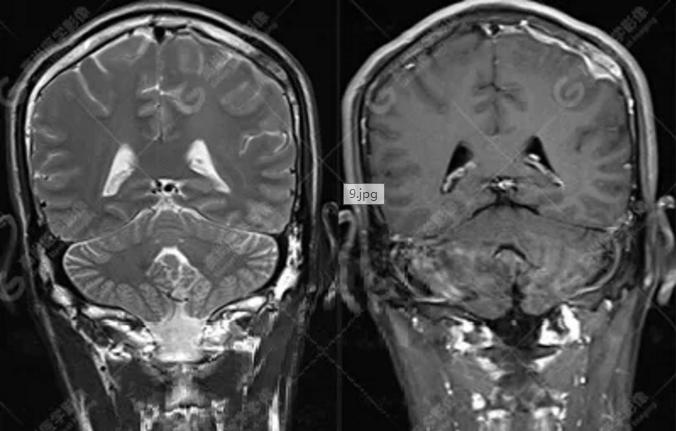

MR圖像

左側(cè)額頂部顱骨骨質(zhì)破壞并相鄰硬腦膜增厚強(qiáng)化,考慮Rosai Dorfman?。≧DD)可能,需與朗格漢斯細(xì)胞組織細(xì)胞增生癥鑒別。

典型的RDD在MRI上T1WI 呈等信號(hào),T2WI及 DWI為等-低信號(hào),增強(qiáng)掃描多為明顯均勻強(qiáng)化,多伴有腦膜尾征,部分病例伴有不同程度的腦水腫。T2WI 像 RDD 病灶中出現(xiàn)聚集的低信號(hào)影及 CT檢查沒有鈣化是 RDD 的特征性影像學(xué)表現(xiàn)。